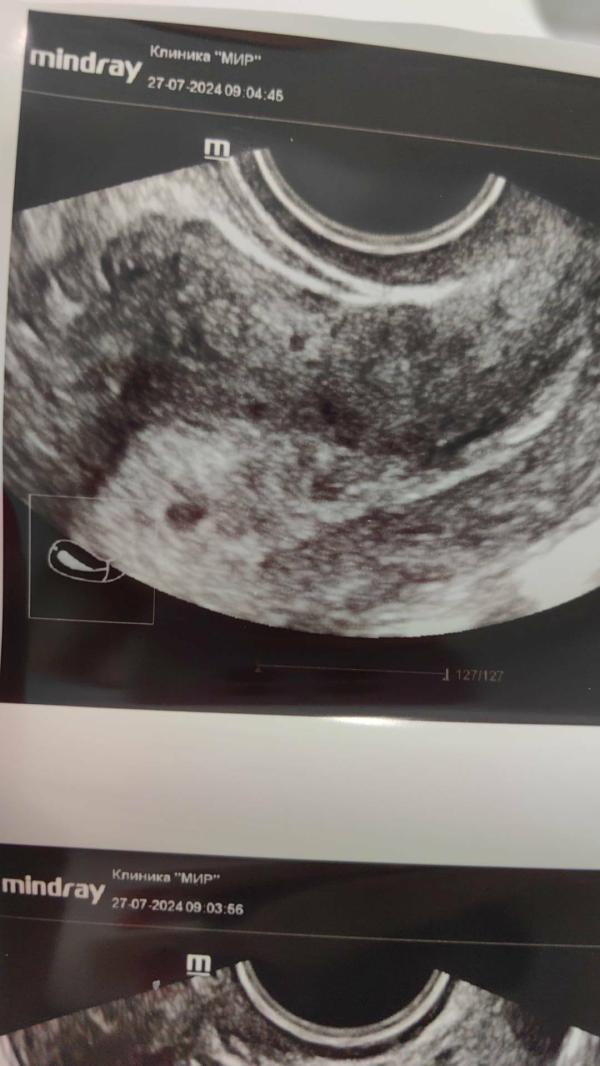

Сегодня 18 дпо и у меня нашли плодное яйцо в полости матки, но не нашли жёлтое тело правого яичника!

Жт в левом яичнике это киста с прошлого цикла

Через 3 дня после овуляции увидели какое то "белое тело" правого яичника, как я поняла это значит полость фоликула, который лопнул и вышла яйцеклетка.

Но без жёлтого тела от этого цикла беременность бы не развивалась, хгч растёт, яичко есть!

Пришёл прогестерон - 84, что прекрасно, теперь интересно, где прячется моё жёлтое тело 😄